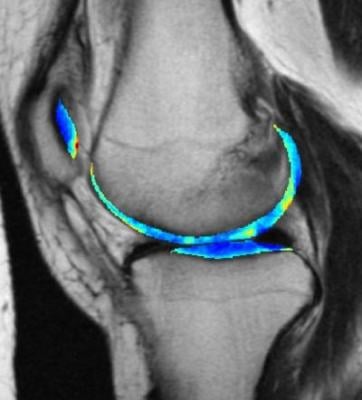

The cartilage in this MRI scan of a knee is colorized to show greater contrast between shades of gray. Image courtesy of Kundu et al. (2020) PNAS

"When doctors look at these images of the cartilage, there isn't a pattern that jumps out to the naked eye, but that doesn't mean there's not a pattern there. It just means you can't see it using conventional tools," said lead author Shinjini Kundu, M.D., Ph.D., who completed this project as part of her graduate training in the Pitt Medical Scientist Training Program and Carnegie Mellon Department of Biomedical Engineering.